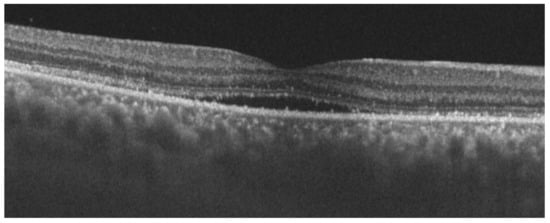

Figure 4.

OCT image of the right eye, showing choroidal thickening and subfoveal neurosensory retinal detachment.